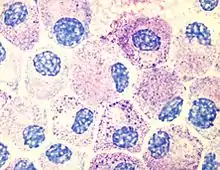

The thumbnail on the right shows the typical features of a cell as seen under with a light microscope using a standard stain. The chief features are a cell membrane, a granular cytoplasm, and a nucleus with in most cases a darker staining nucleous.

To see other features usually requires special stains, or an electron microscope.